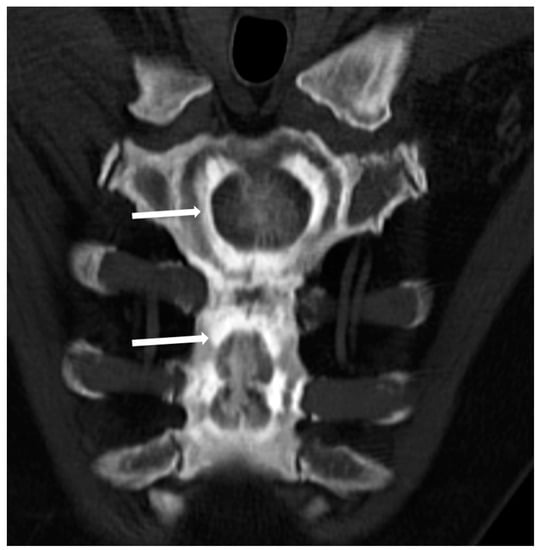

(3) The so-called ‘bone-within-a-bone’ or ‘bone-in-bone’ appearance, characterized by the presence of focal areas of sclerosis within a skeletal segment resembling another bone within the affected bone (Figure 3), which can be mostly found in phalanges, vertebrae, iliac wings, and long bones.

This peculiar imaging feature is more frequently found in ADO type 2 of osteopetrosis, but it can also be encountered in radiological studies of patients affected by ARO and IAO forms.

Figure 3. Computed Tomography (CT, coronal-oblique reconstruction) of the sternum in a 48-year-old male affected by osteopetrosis (ADO type 2). The so-called ‘bone in bone’ appearance is detectable with a well-defined increased density within the skeletal segment involved (arrows).